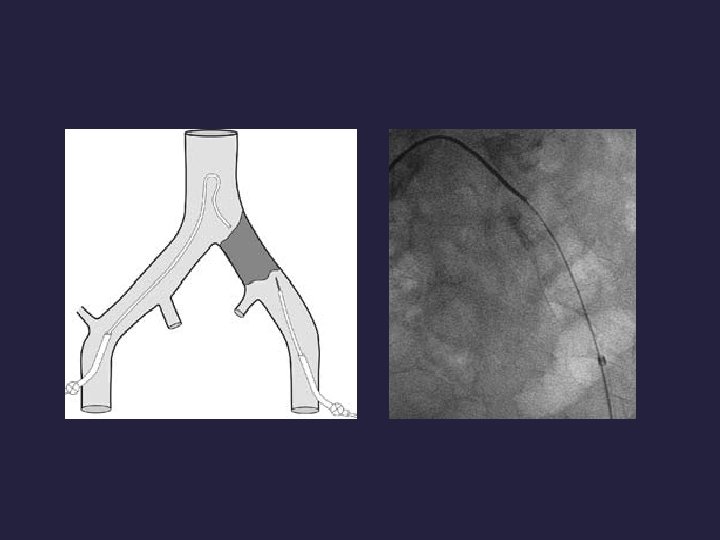

Yöntem: • Retrograd girim/antegrad girim (gerekirse brakiyal arter girim) • Bentson tel ( Boston Scientific, Natick, MA, USA) • 0. 035 -in. hidrofilik tel (Glidewire, Terumo, Tokyo)

• Predilatasyon (hekim tercihine göre) • Stent ve post dilatasyon • Kendinden açılır • Balonla açılır • 6 -10 mm • Balon boyutu (stentle aynı/1 mm küçük)